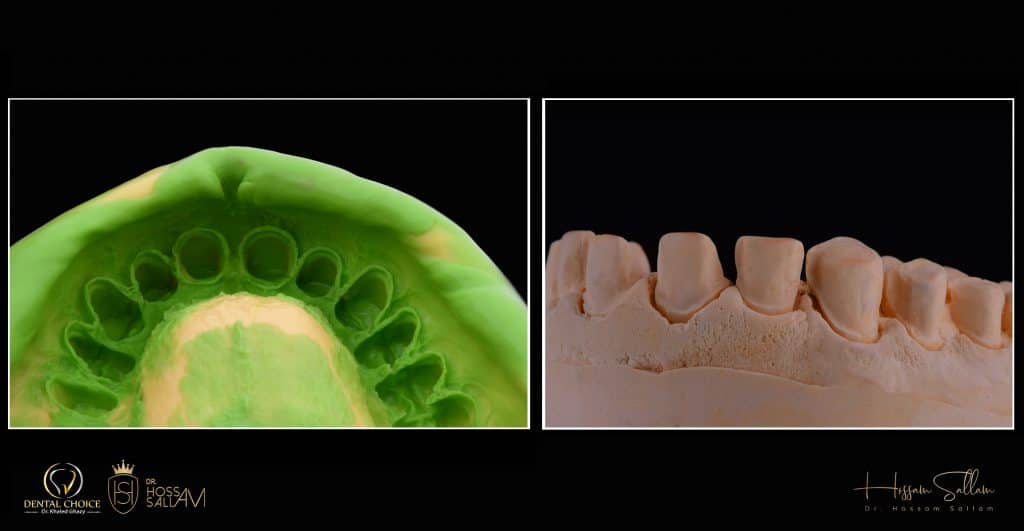

Additional Silicone material is the best choice here to get the best details

i prefer using Veneer me

it helps me and save more time